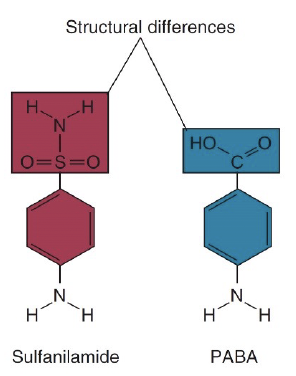

- Protosil (Sulfanilamide)

- Sulfanilamide

- 類似PABA

- 類似PABA